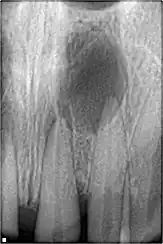

une infection bactérienne de la dent visible sur la radiographie dentaire